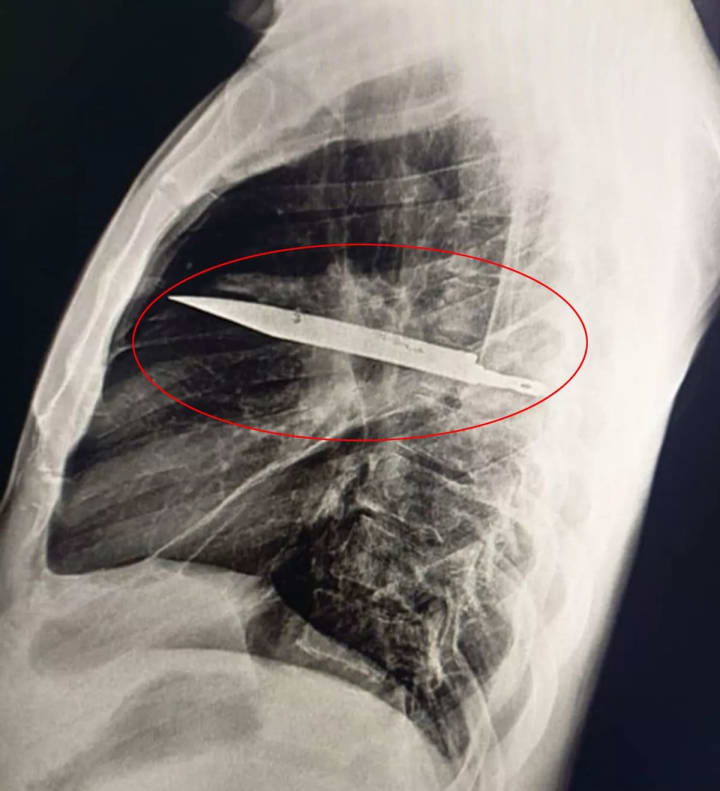

Initially baffled, doctors ran a series of diagnostic tests, including a chest radiograph (X-ray). The results stunned the medical team—there was a large knife blade lodged in the mid-thorax, perilously close to major organs.

The key lies in the placement of the blade. According to the surgical team, the knife:

Entered through the right scapula (shoulder blade)

Missed major organs, arteries, and the heart

Remained lodged in a way that caused minimal disturbance to surrounding tissues